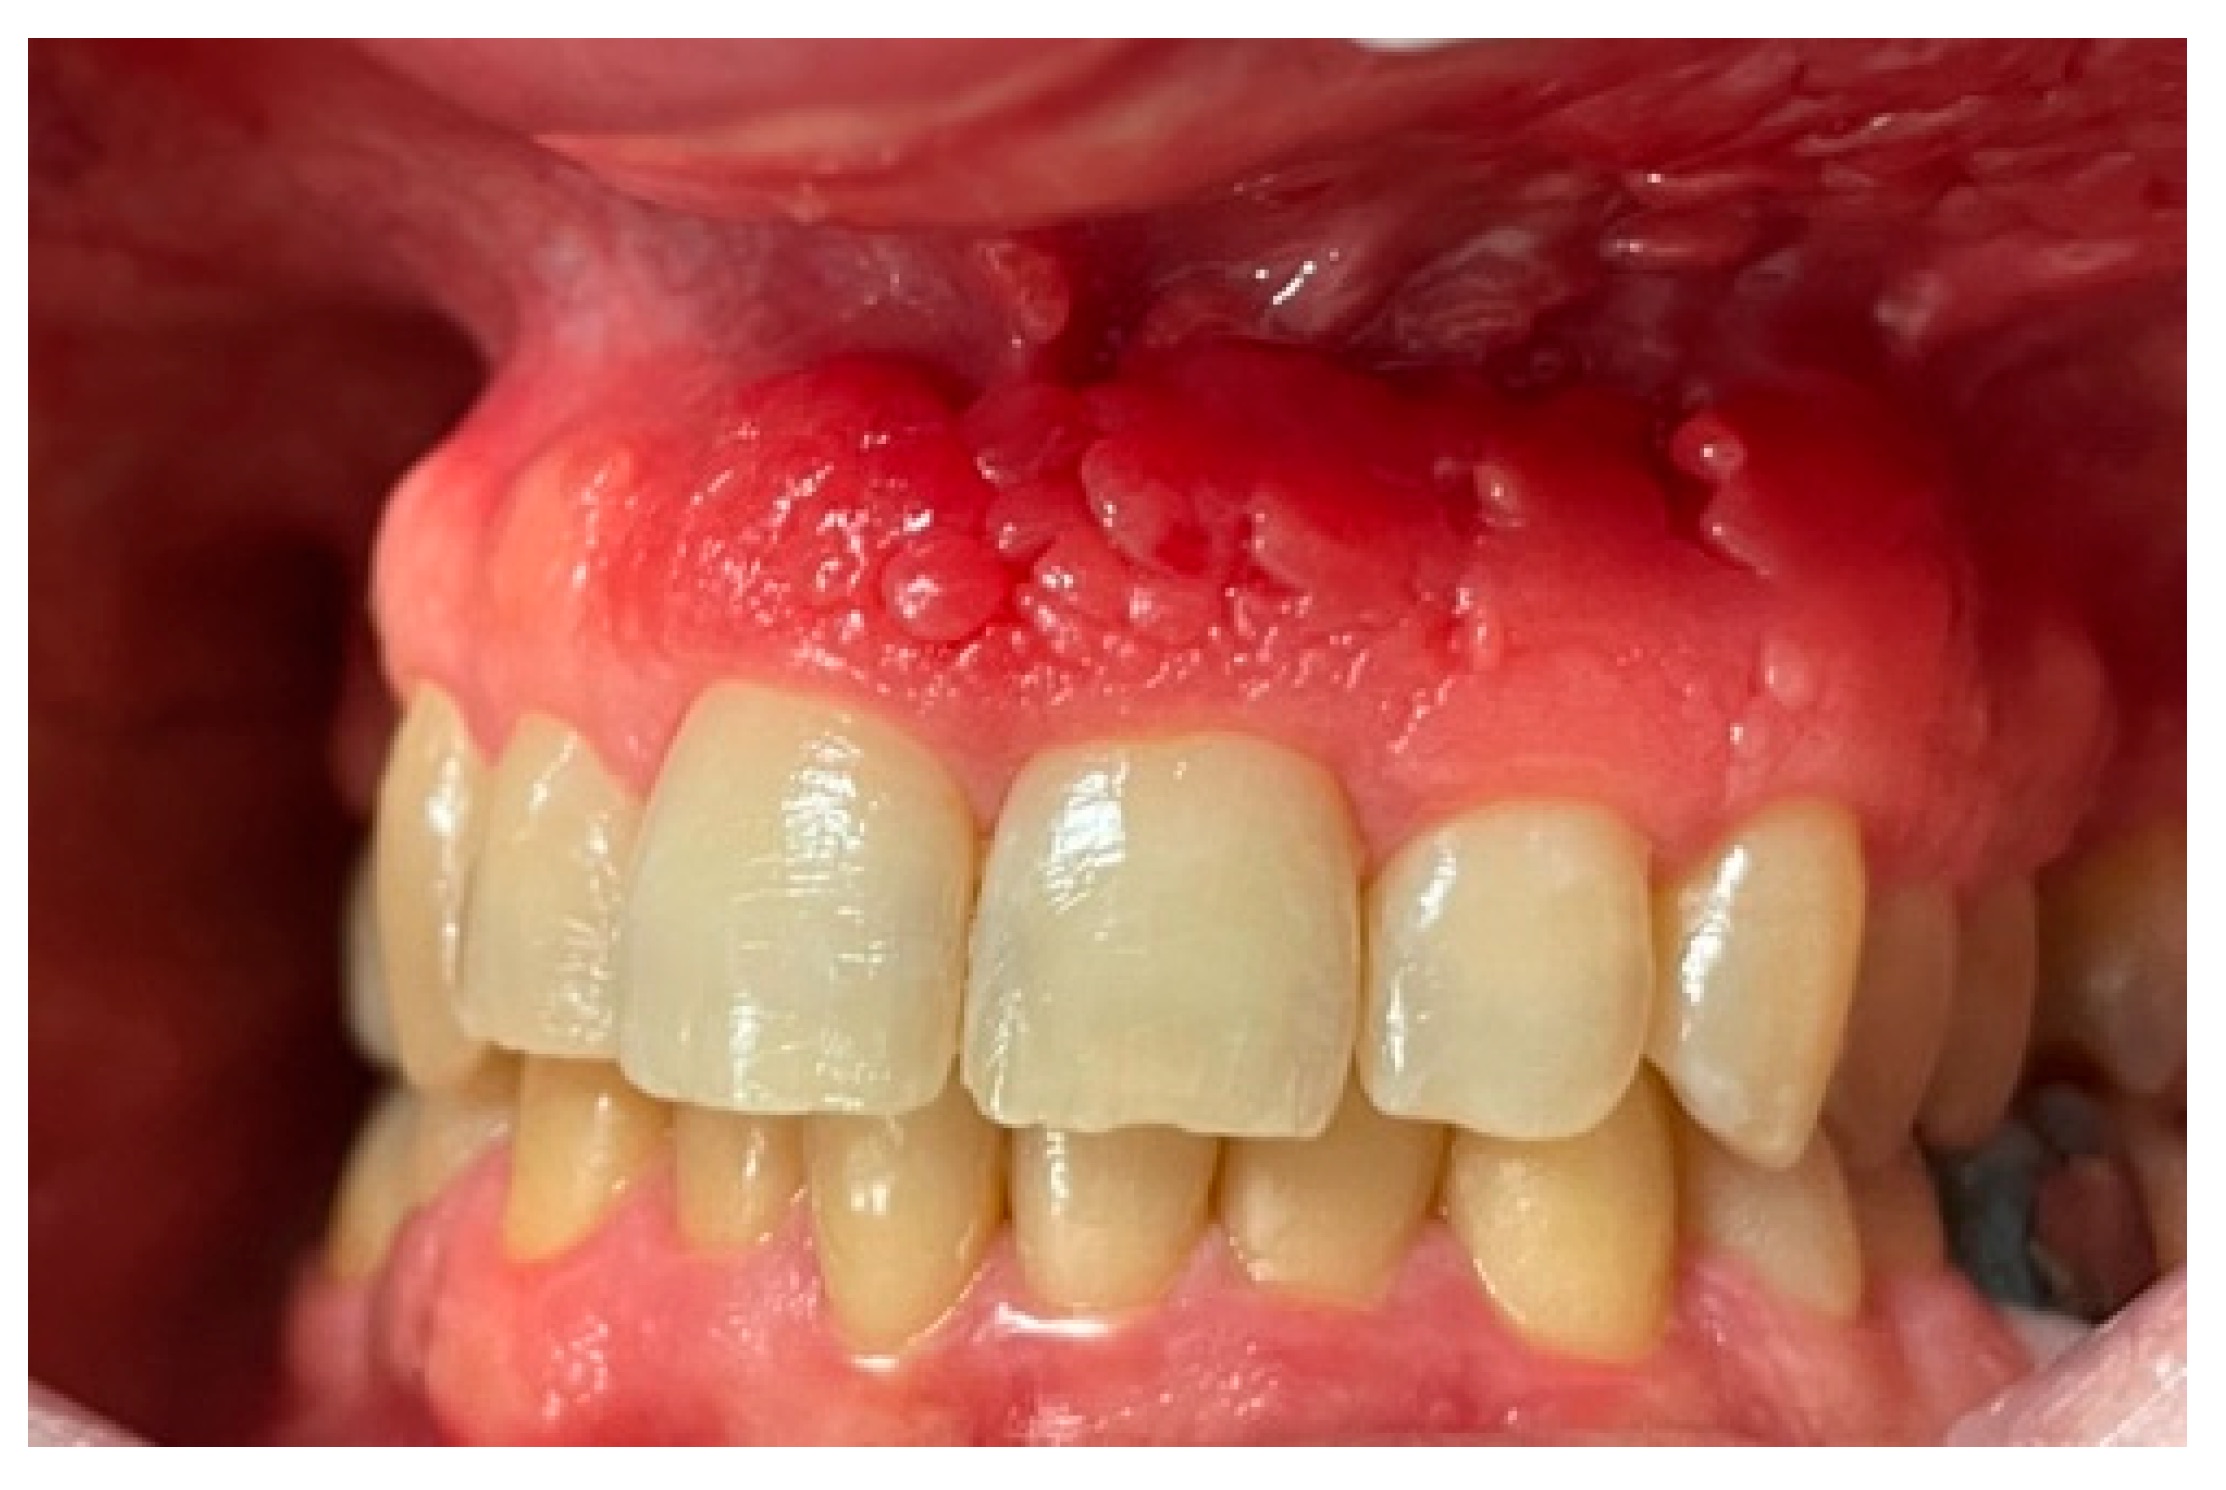

- Extra-oral: Localized right buccal swelling

- Intra-oral: Bluish discoloration over the posterior mandibular ridge

- No airway compromise, dysphagia, or limitation of mouth opening